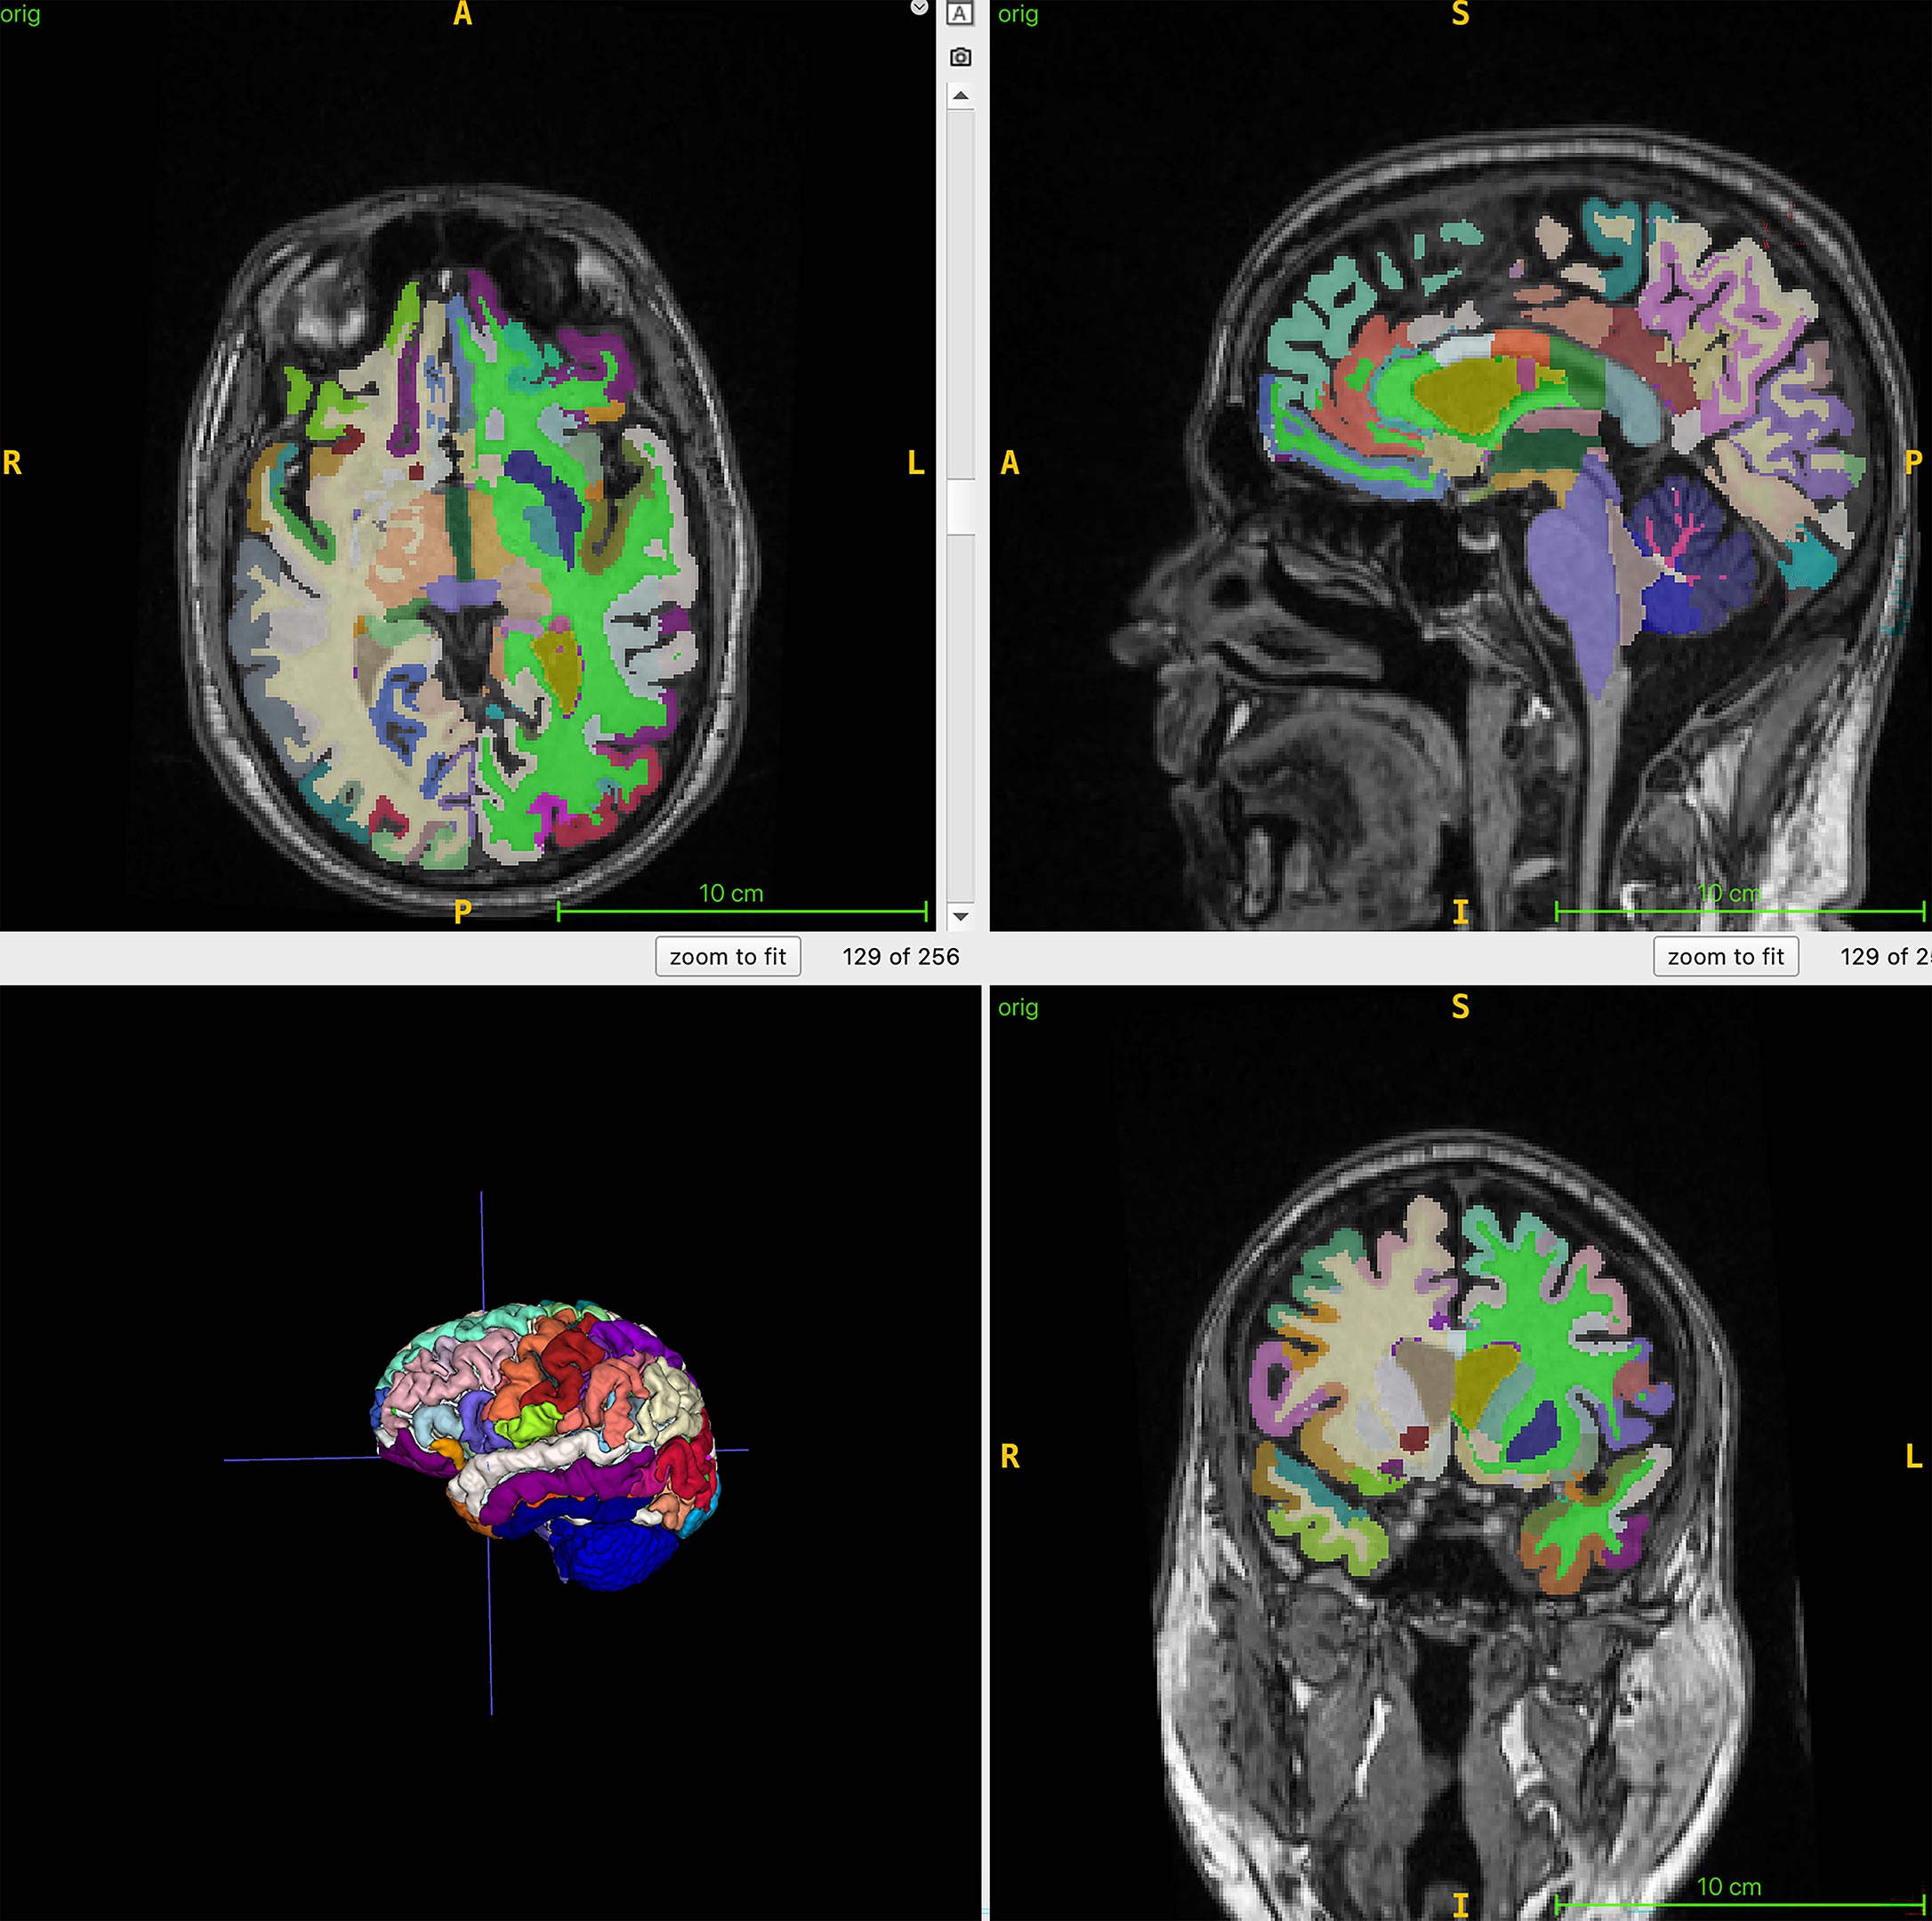

عمر الدماغ هو العمر البيولوجي المقدر للدماغ بناءً على فحص التصوير بالرنين المغناطيسي الهيكلي. يمكن أن تكون كتلة العضلات التي يتم قياسها من خلال التصوير بالرنين المغناطيسي للجسم بمثابة مؤشر للتدخلات التي تهدف إلى تقليل الضعف ودعم صحة الدماغ، في حين أن عمر الدماغ المحسوب من الصور الهيكلية قد يساعد في تحديد عوامل خطر مرض الزهايمر، بما في ذلك فقدان العضلات.

وفي البحث المستمر، تم إجراء فحوصات التصوير بالرنين المغناطيسي لكامل الجسم على 1,164 من البالغين الأصحاء (52% من النساء) في أربعة مواقع. وكان متوسط العمر الزمني للمجموعة 55.17 سنة. استخدم الفريق التصوير بالرنين المغناطيسي مع تسلسلات مرجحة T1، والتي تسلط الضوء على الدهون الساطعة والسوائل مثل الظلام، مما يسمح بتصور واضح للعضلات والدهون وأنسجة المخ. ان الذكاء الاصطناعي ثم قامت أداة (AI) بقياس إجمالي حجم العضلات الطبيعي، والدهون الحشوية (دهون البطن المخفية)، والدهون تحت الجلد (الدهون تحت الجلد) وعمر الدماغ.